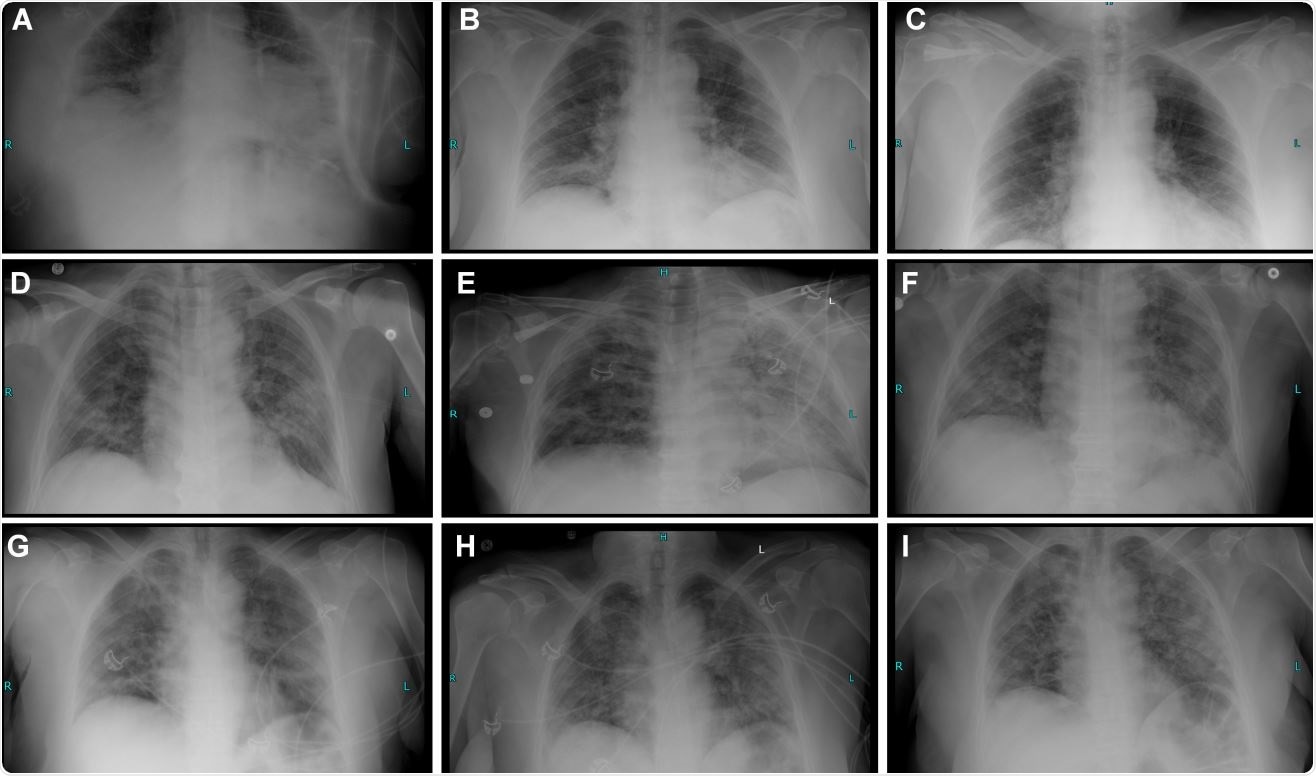

Radiography timeline and clinical course description of 3 COVID-19 cases treated with hemofiltration.